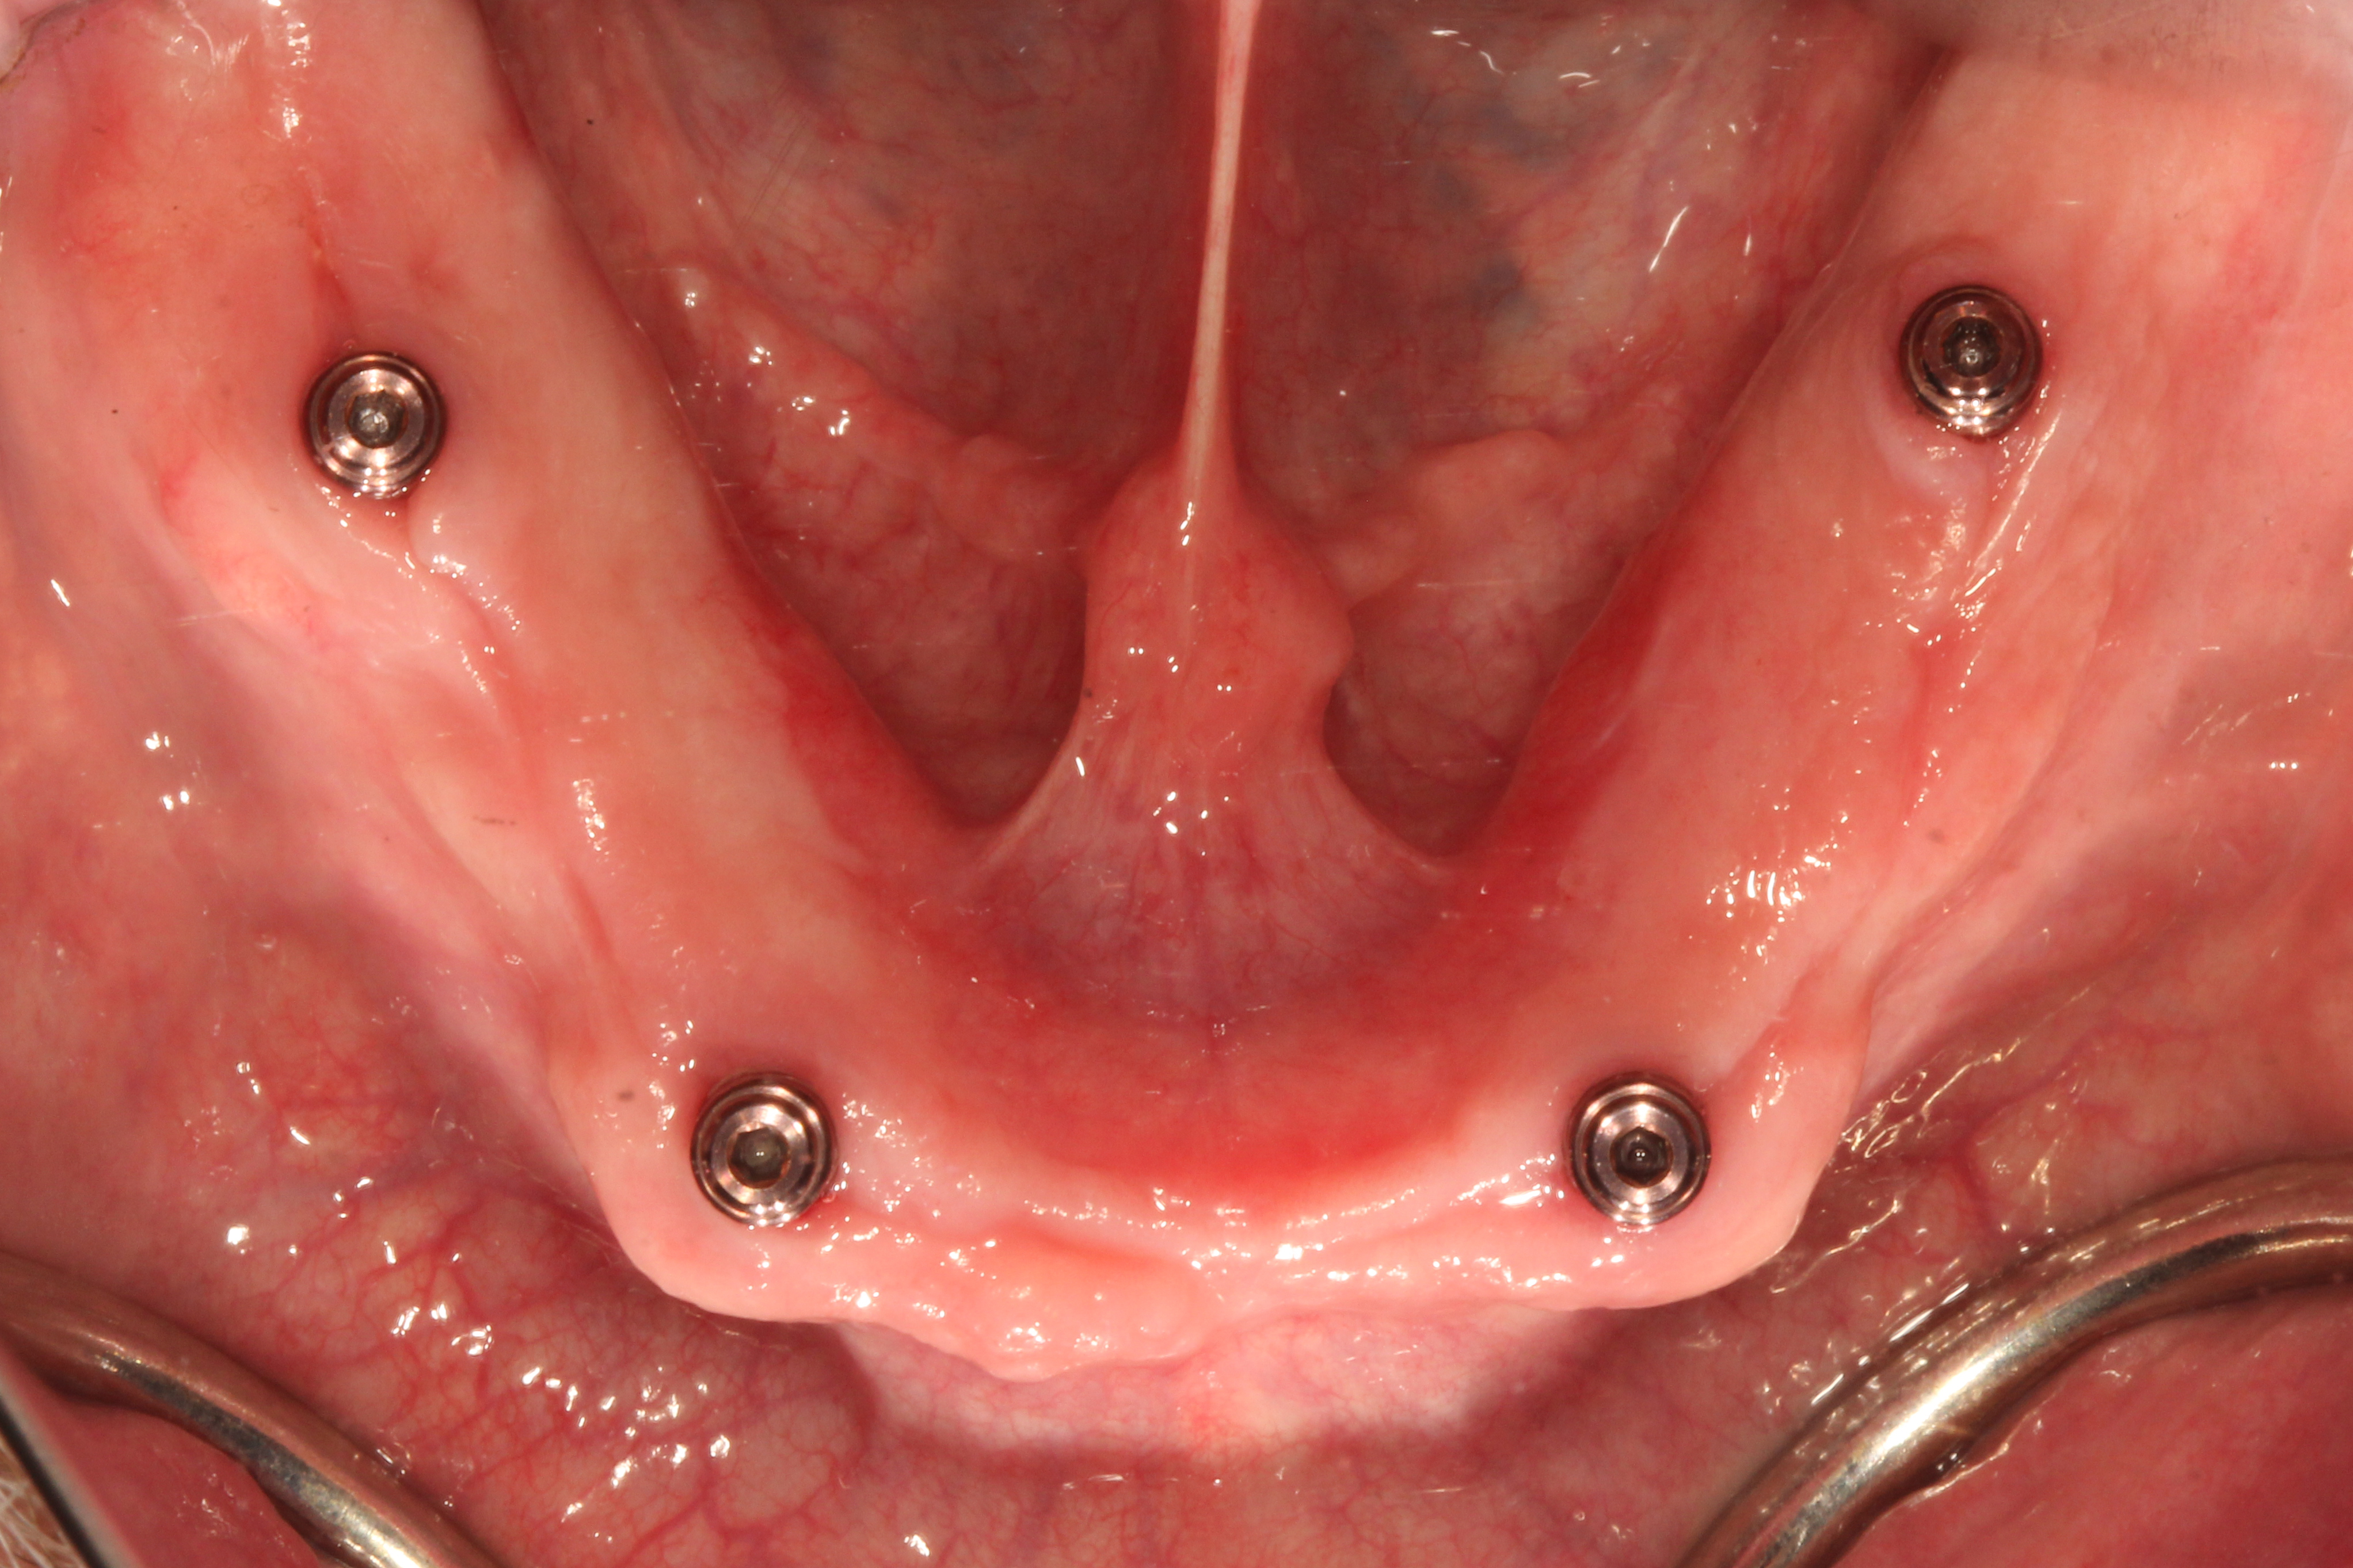

As a result of this discussion, a treatment plan of six implants on the maxillary arch and four implants on the mandibular arch was presented. The patient agreed to the treatment, and the teeth were extracted and dental implants (ET III, Hiossen) were placed in the tooth No. 2/3, 4/5, 7, 10, 13/14, 14/15 positions on the maxillary arch and the tooth No. 19, B, D, 30 positions on the mandibular arch. After osseointegration, definitive stud-style abutments (LOCATOR R-Tx) were placed and torqued according to the manufacturer's recommended torque value on implants in the maxillary and mandibular arches (Figure 8 and Figure 9).

Fig 8. Definitive stud-style abutments (LOCATOR R-Tx, Zest Dental Solutions) were placed onto the mandibular implants.

Figure 8

Fig 9. Definitive stud-style abutments (LOCATOR R-Tx, Zest Dental Solutions) were placed onto the mandibular implants.

Figure 9